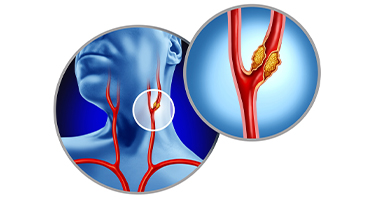

Carotid Artery Stenting vs Endarterectomy: Which Is Better for You

Stroke is a serious condition that happens when a blood clot or broken vessel prevents blood from reaching the brain. Due to this, one can experience paralysis, muscle weakness, slurred speech, and memory challenges, or even seizures.

Carotid Stenting: A Life-Saving Procedure to Prevent Stroke

You might face many instances in life where planning ahead could make all the difference. For example, if you want to crack a competitive exam, you analyze the past papers, concentrate most on the important topics, and then study hard to get the best outcome.